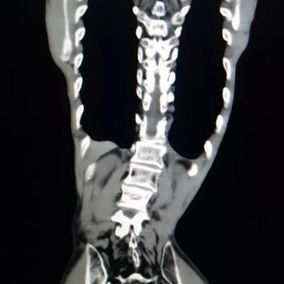

After a preoperative examination, it is observed that the patient's anterior chest wall protruded severely, reaching its peak at the xiphoid process, which presented as a 90-degree angle when viewed from the side. The heart is displaced to the right chest cavity, and the torso is severely deformed, characterized by a broad chest and a noticeably narrowed waist and abdominal area. The narrowing is most pronounced above the pelvis. Moreover, a chest CT scan reveals two large cysts located between the heart and the anterior chest wall in the lower lobe of the left lung, measuring 7x8 cm and 9x10 cm respectively.